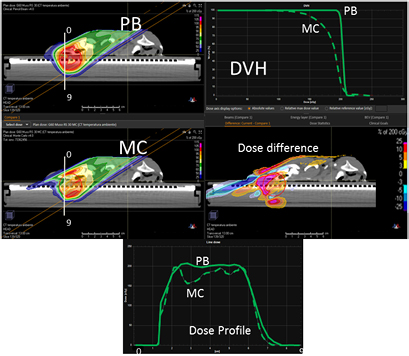

In figure 4, on the top we have the PB dose distribution optimized with our TPS that showed a good uniformity and conformity to the target of the 1/6 head phantom for a proton field angle of 70° and snout position 42 cm from the isocenter. The MC recalculation of the experimental setup (oblique field and superficial target on the anthropomorphic phantom) showed significant differences with respect to the PB calculation, with under-dosage up to 25% in the target and over-dosage up to 30% outside the target.

Figure 4. PB optimized dose distribution on the 1/6 head phantom (top left) and the MC recalculation (middle left) with a proton field angle of 70° and the RS 42 cm from the isocenter (i.e. air gap ~24 cm). The white lines represent the dose profiles' (bottom) extraction plans. On the right side of the figure, the DVHs of both the dose distributions (top right) and dose difference (middle right) are displayed.

Figure 6 reports the PB dose distribution of a plan optimized on the two slabs of the head phantom and its MC recalculation.

Figure 6. PB optimized dose distribution on the 2/6 head phantom (top left) and MC recalculation (middle left) with a proton field angle of 70° and the RS 42 cm from the isocenter (i.e. air gap ~26 cm). The white lines represent the dose profiles' (bottom) extraction plans. On the right side of the figure, the DVHs of both the dose distributions (top right) and dose difference (middle right) are displayed.

Figure 8 presents the plan optimized and calculated with the PB algorithm for the brain target of the lamb's head with a gantry angle of 0° and the RS 30 cm from the isocenter. MC recalculation shows significant differences in the dose volume histogram (DVH) and mostly located in the distal part of the target.

Figure 8. PB optimized dose distribution on the brain target of the lamb head (top left) and MC recalculation (middle left) with a proton field angle of 0° and the RS 30 cm from the isocenter (i.e. air gap ~20 cm). The white lines represent the dose profiles' (bottom) extraction plans. On the right side of the figure, the DVHs of both dose distributions (top right) and dose difference (middle right) are displayed.

Figure 10. PB optimized dose distribution on the nose target of the lamb's head (top left) and MC recalculation (middle left) with a proton field angle of 60° and the RS 30 cm from the isocenter (i.e. air gap ~7.5 cm). The white lines represent the dose profiles' (bottom) extraction plans. On the right side of the figure, the DVHs of both the dose distributions (top right) and dose difference (middle right) are displayed.

Download figure: